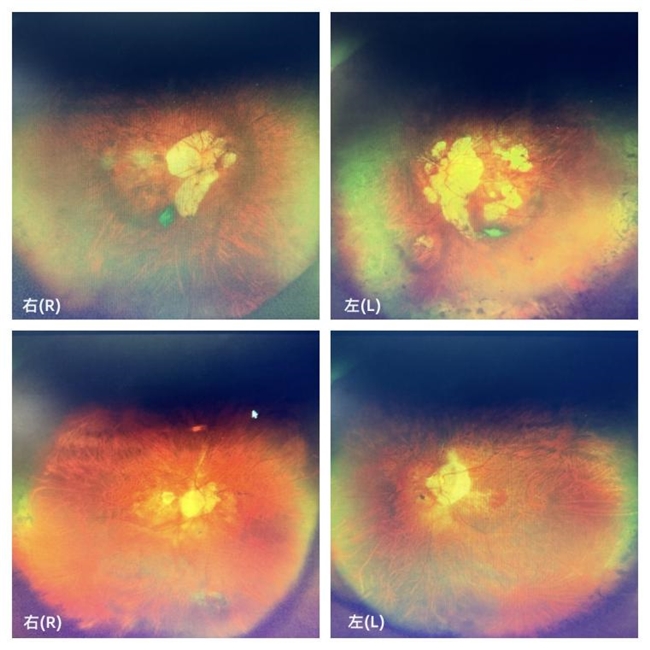

经详细检查,肖爷爷的情况颇为复杂:他不仅有多年的高血压病史,糖尿病史也长达10余年,用药也并不规律。术前检查显示,其左眼视力仅剩0.02,且伴有2100度的超高度近视和250度的散光;右眼视力更差,仅能感知眼前的手指晃动。双眼的眼轴都超过30mm以上,眼底检查还发现肖爷爷双眼均有高度近视相关的眼底病变,除了大面积的视网膜萎缩斑以外,左眼还存在黄斑出血及视网膜劈裂。综合各项检查结果,肖爷爷被明确诊断为:双眼超高度近视伴并发性白内障,同时伴有左眼黄斑出血。

(此图为两人眼底检查图)

在哥哥的鼓励下,弟弟也来到天津普瑞眼科医院就诊。经门诊详细检查,其眼部情况同样复杂:双眼高度近视病史长达60余年,同时患有高血压15年和糖尿病20余年。术前检查显示,其右眼视力仅为0.04,左眼仅能感知眼前手指的晃动;同时,双眼均伴有高度近视眼底病变,且右眼存在黄斑前膜。综合各项检查结果,弟弟被明确诊断为双眼并发性白内障合并超高度近视,并伴有双眼玻璃体混浊。